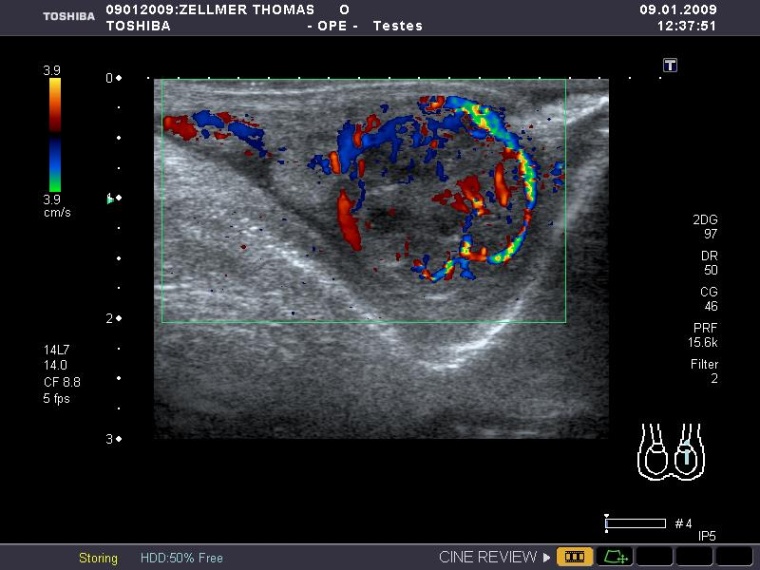

Wenn auch sehr selten, können ebenso tumoröse Veränderungen am Hoden das Bild eines „akuten Skrotums“ imitieren. Gerade die Ultraschalldiagnostik ist richtungsweisend bei diesem Krankheitsbild. Wie im Falle des Granulosozelltumors lässt sich eine inhomoge, teils zystische Raumforderung im Hoden abgrenzen, welche eine Hyperperfusion aufweist.